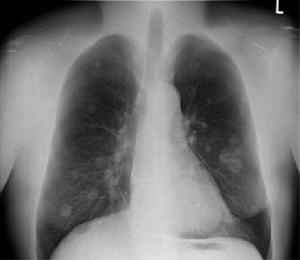

診斷:老年終末期肺炎大多數缺乏典型症狀和體徵,診斷主要依據肺部X線,有小片狀陰影,結合肺部可聞及水泡音,即可診斷。

2.影像學 終末期肺炎由於症狀、體徵不明顯,故診斷主要依據X 線,多顯示小片狀陰影,沿支氣管走行,右下肺為著,但臨床上也可聽到肺部可聞及明顯的水泡音,而胸片炎症徵象不明顯者,可能與長期臥床、炎性分泌物積聚到脊柱旁導致炎症陰影顯示不清有關。除此以外如合併心衰可見心影增大,並可見胸腔積液徵象,其原因考慮由於胸膜炎症反應,低蛋白血症及心衰綜合因素所致。